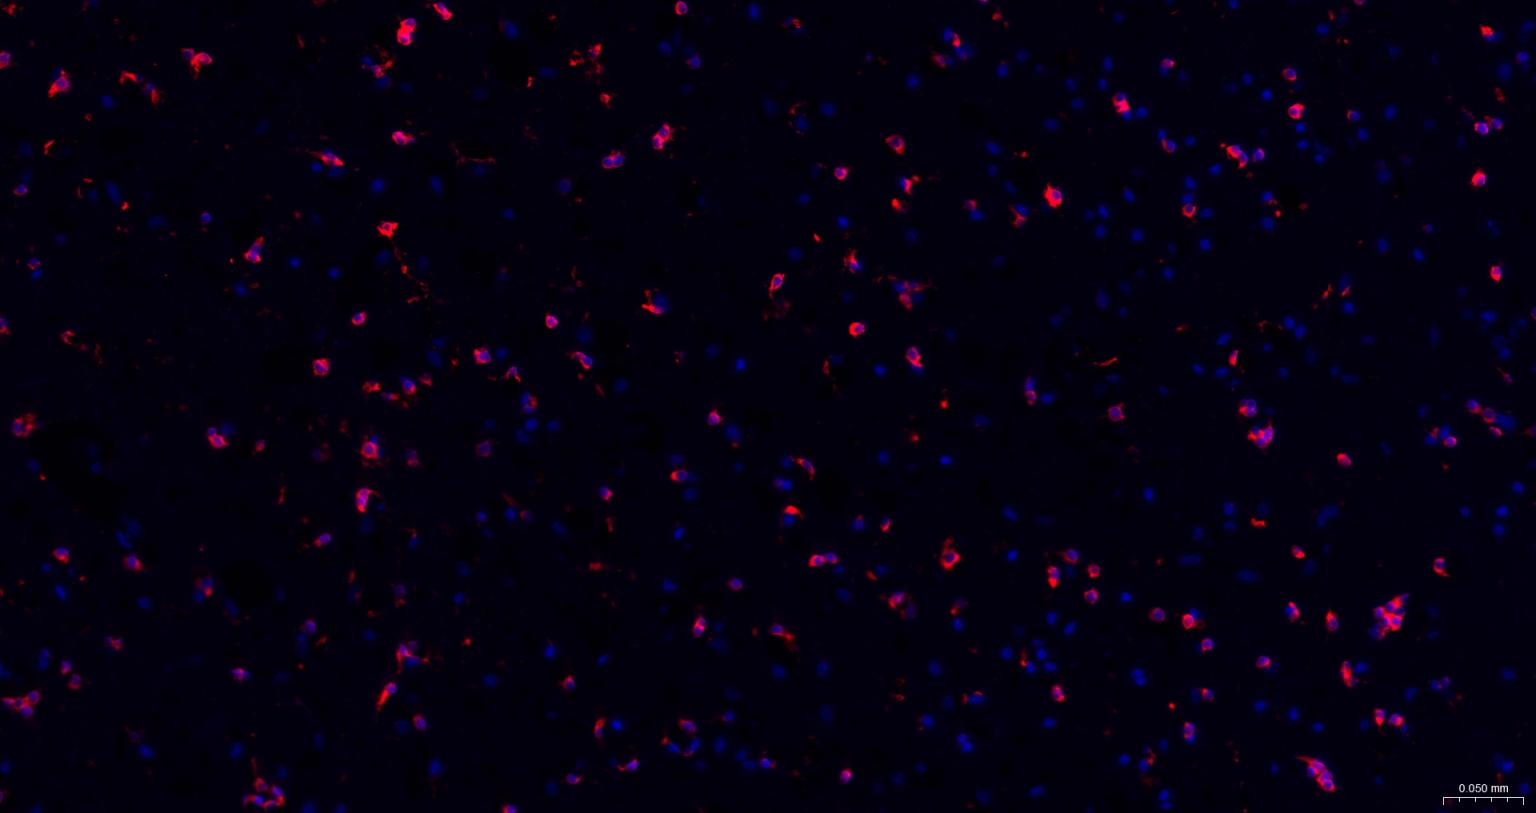

Paraformaldehyde-fixed, paraffin embedded Mouse Cerebrum; Antigen retrieval by boiling in sodium citrate buffer (pH6.0) for 15 min; The section was incubated with NMDAR1 Monoclonal Antibody, Unconjugated (bsm-52950R) at 1:200 overnight at 4°C. Followed by conjugated Goat Anti-Rabbit IgG antibody (Red, bs-0295G-BF594), DAPI (blue, C02-04002) was used to stain the cell nuclei.